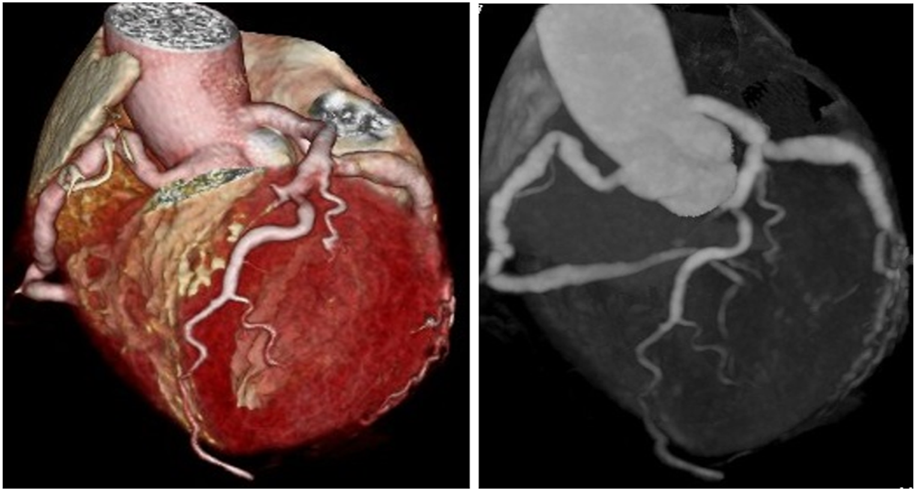

FIGURE 2

Two types of coronary CT angiography (volume-reproduction model) show diffuse coronary ectasia.